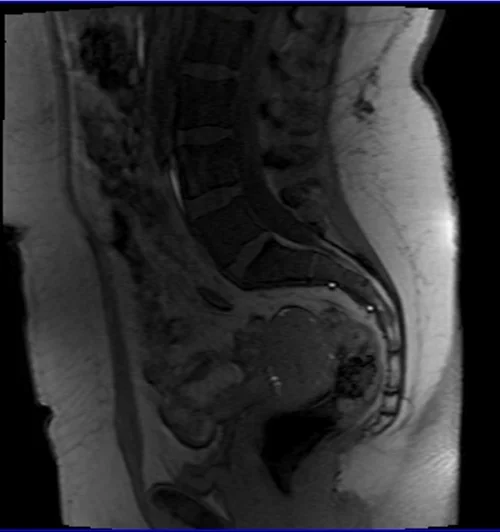

mri sij loc 2 - MRI